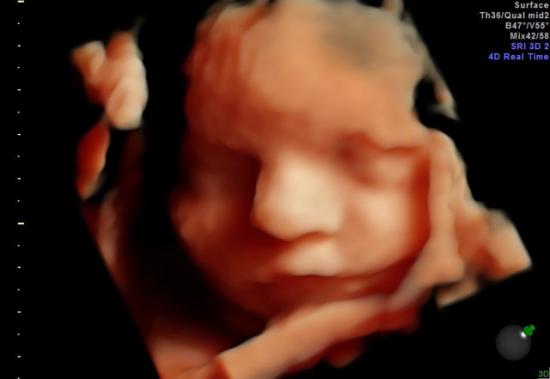

- badanie III trymestru (USG) wykonywane między 28-32 t.c.

Badanie to polega na ocenie anatomii płodu, parametrów biometrycznych, oszacowaniu masy płodu oraz oceny przepływów w sercu i łożysku.